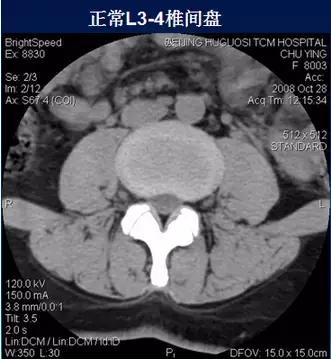

常规腰椎CT扫描层面

常规腰椎CT扫描L3-S1段,分为

(2)椎间盘层面(软组织窗):观察椎间盘、硬膜囊、神经根、韧带等软组织。

二、椎间盘膨出

椎间盘影均匀超出相应椎体边缘,轻度时CT表现为间盘后缘正常肾形凹陷消失,圆隆饱满。